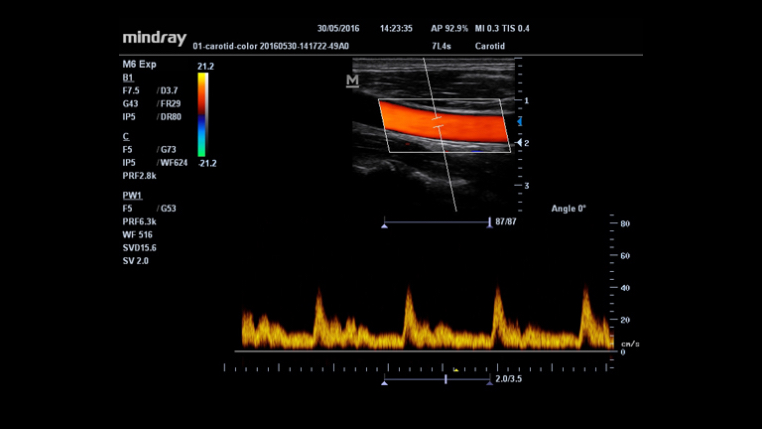

Smart Track (Inteligentny obrys)

Unikalna funkcja Firmy Mindray: Ci?g?e ?ledzenie naczynia z przep?ywem w trybie Dopplera kolorowego wraz z jednoczesn? optymalizacj? pozycji bramki (ROI) Dopplera kolorowego i?k?ta ustawienia bramki (pochylenie wi?zki ultrad?wi?kowej) podczas skanowania w czasie rzeczywistym.